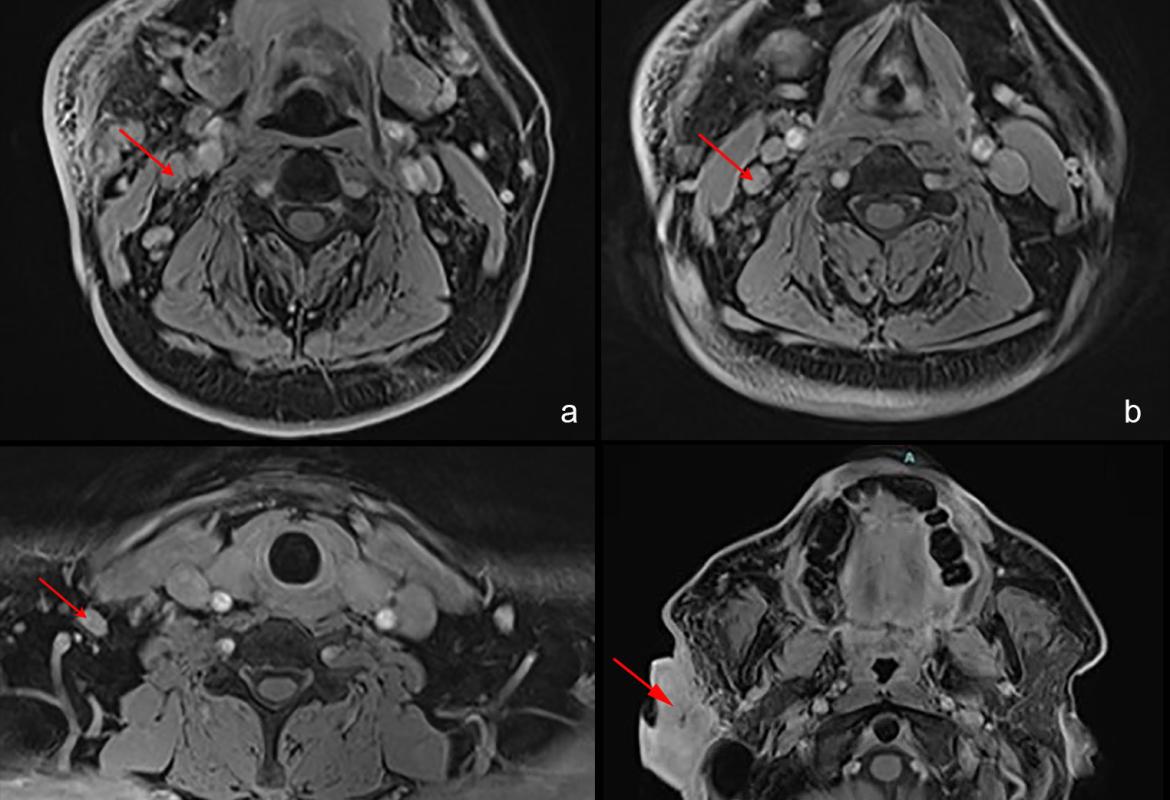

FIGURE 2: MRI images showed (a-c) enlarged and enhancing lymph nodes at levels 2, 3, and 4 of the right cervical neck regions; (d) lobulated soft tissue mass measuring 2.6 cm x 4.9 cm x 6.3 cm in the right pre- and postauricular space